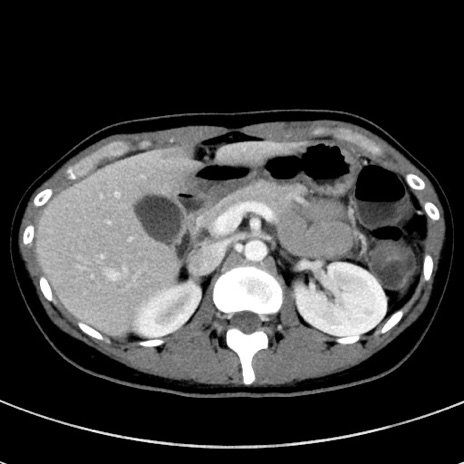

症例17(横断像)

【症例】20歳代女性

【主訴】嘔吐、下腹部痛

【現病歴】昨日夕食後に嘔吐し下腹部痛が出現。本日になっても嘔吐持続し改善しないため来院。

【身体所見】意識清明、BT 37.2℃、BP 108/67mmHg、腹部:平坦、やや硬、下腹部正中から右にかけて圧痛あり、反跳痛軽度あり、tapping pain(+)。

【データ】WBC 13600、CRP 14.94